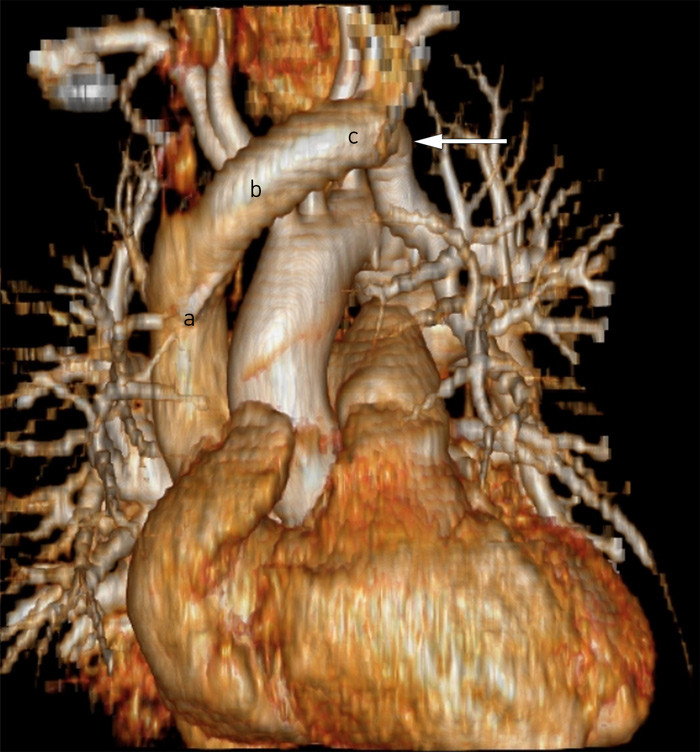

Varying values may indicate that the blood in the superior vena cava is not fully mixed, such that the location of sampling can greatly affect the results.

The anatomical anomaly possessed by the patient causes highly oxygenated blood from the lung to drain into the venous system. Functionally, this is equivalent oxygenation-wise to a large left-to-right shunt, which explains the almost identical SO₂ values in arterial and venous blood gases.

Upon reassessment of earlier echocardiographic images (both transoesophageal and transthoracic), calculations revealed right ventricular cardiac output to be approximately 34 % greater than left ventricular output. In addition, septal flattening during diastole suggested elevated pressure in the right ventricle. CT images also showed a dilated left brachiocephalic vein with diameter 18 mm, which is about 50 % larger than normal. This is consistent with the substantially increased flow through the vessel.

Partial anomalous pulmonary venous connection (PAPVC) is a rare congenital anomaly, with an incidence of 0.4 to 0.7 % (5, 6). In PAPVC, one or more pulmonary veins are typically connected to the right atrium or vena cava instead of to the left atrium, allowing oxygenated blood to flow back to the right heart; the anomaly is thus analogous to a left-to-right shunt. Isolated PAPVC (with no atrial septal defect) is rare, and most often involves the upper right pulmonary vein draining into the superior vena cava. The anomaly in our patient, with involvement of the left pulmonary vein and drainage to the left brachiocephalic vein, is seen in approximately 3 % of those with PAPVC (5), and is thus very rare. Symptoms are dependent on how many pulmonary veins drain into the right side of the heart. A single anomalous vein is rarely haemodynamically significant and therefore often gives no symptoms (5), but nevertheless represents an increased strain on the right ventricle.

The first catheter was positioned distally in the superior vena cava, such that powerful reflux from an atrial septal defect could conceivably produce a high ScvO2 value. However, the next two catheters were positioned more proximally in the superior vena cava, and it is difficult to explain high central venous saturation here in the same way (Figure 1).